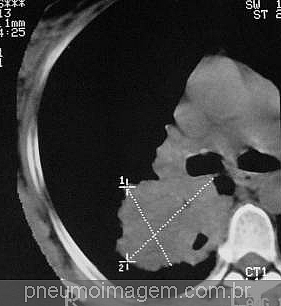

RASTREAMENTO DO CÂNCER DE PULMÃO: NOVAS RECOMENDAÇÕESA diretriz sobre a triagem do câncer de pulmão lançada pela Canadian Task Force on Preventive Health Care (CTFPHC) foi atualizada. A triagem anual com tomografia computadorizada de baixa dose é recomendada por até 3 anos consecutivos para o rastreamento de câncer de pulmão para os seguintes grupos abaixo:

1. Pacientes adultos entre 55 e 74 anos de idade com alto risco de câncer de pulmão podem beneficiar-se com o rastreamento tomográfico de baixa radiação durante 3 anos consecutivos (deve-se discutir com o paciente a respeito dos riscos e benefícios do método);